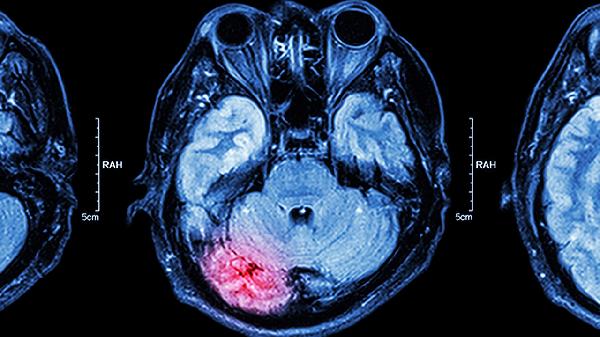

3、改善脑循环

心脑舒通片能扩张脑血管,增加脑部血流量,改善脑组织供氧。对于脑供血不足引起的头晕、头痛、记忆力减退等症状有缓解作用。该药物通过调节血管功能,帮助维持脑部正常代谢活动。